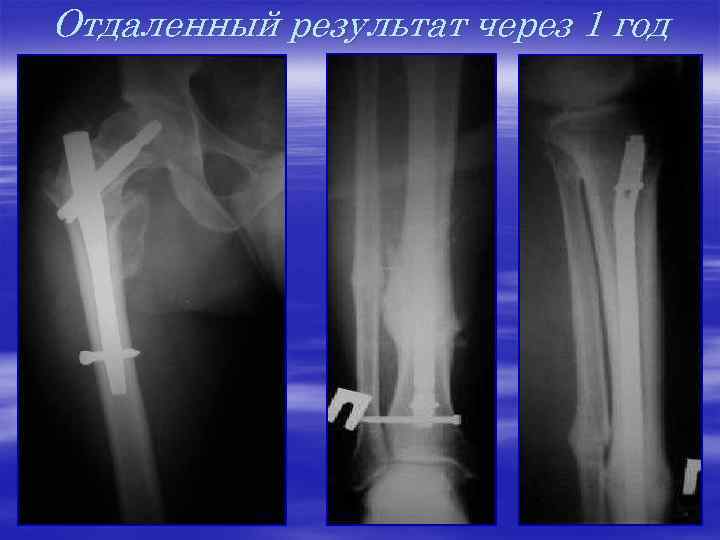

Одномоментный последовательный остеосинтез коротким гамма-штифтом, блокируемым штифтом б/б к (T 2) на одноименной стороне

Отдаленный результат через 1 год